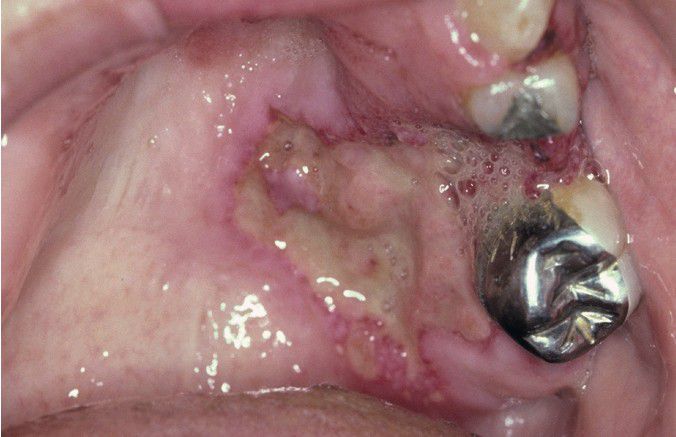

Wegener Granulomatosis

. Deep, irregular ulceration of the hard palate on the left side.